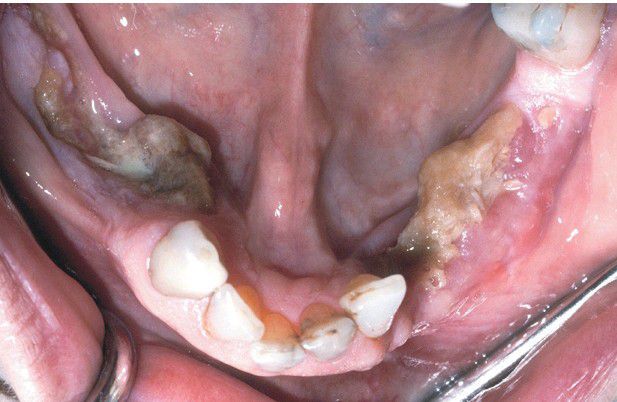

Medication-related Osteonecrosis

. Bilateral necrotic exposed bone of the mandible in a patient receiving zoledronic acid for metastatic breast cancer.